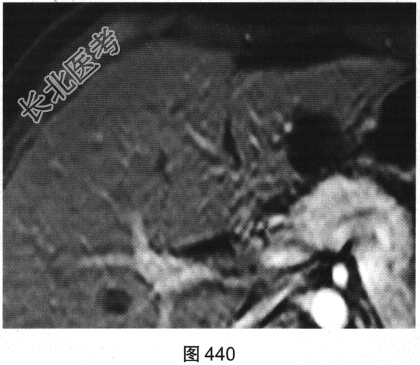

- 多项选择题3.[提示]增强扫描后的病变见图440、图441。此时考虑的诊断为( )

A、肝细胞癌

B、胆管细胞癌

C、肝囊肿

D、肝腺瘤

E、肝脓肿

F、肝海绵状血管瘤

关注下方微信公众号,搜题查看答案